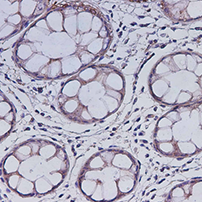

- 货号:E-AB-18160

- 宿主:Rabbit

- 反应性:Human;Mouse;Rat

- 应用性:IHC

- 货号:E-AB-18162

- 宿主:Rabbit

- 反应性:Human;Mouse;Rat

- 应用性:IHC

- 货号:E-AB-18164

- 宿主:Rabbit

- 反应性:Human;Mouse;Rat

- 应用性:IHC

- 货号:E-AB-18169

- 宿主:Rabbit

- 反应性:Human;Mouse;Rat

- 应用性:IHC

- 货号:E-AB-18171

- 宿主:Rabbit

- 反应性:Human;Mouse;Rat

- 应用性:IHC

- 货号:E-AB-18172

- 宿主:Rabbit

- 反应性:Human;Mouse;Rat

- 应用性:IHC

- 货号:E-AB-18176

- 宿主:Rabbit

- 反应性:Human;Mouse;Rat

- 应用性:WB;IHC

- 货号:E-AB-18183

- 宿主:Rabbit

- 反应性:Human;Mouse;Rat

- 应用性:WB;IHC